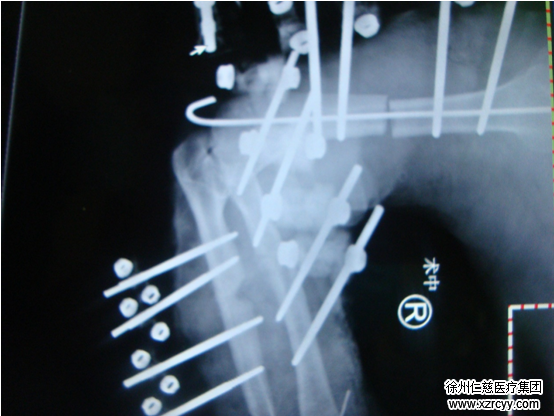

术中情况

时间是再植成功的保证,为提高成功率,术中黎章灿医生和潘勇医生“兵分两路”:一组清创残肢、行尺桡骨骨折复位内固定、外固定;一组行上臂残端清创。

“由于人体的血管、神经结构特殊,再植,特别是大肢体离断必须保证吻合血管通畅,神经对接良好,容不得丝毫马虎。”伤口清创、骨支架固定、血管的修复处理……争分夺秒近5个小时,经过一系列的操作,再植肢体的皮温逐渐上升,右上肢成功被保住。

术中修复